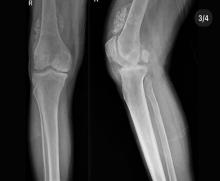

Düzce Üniversitesi Tıp Fakültesi Hastanesi Ortopedi ve Travmatoloji Kliniği’nde gerçekleştirilen operasyonda, eklem faresi olarak da